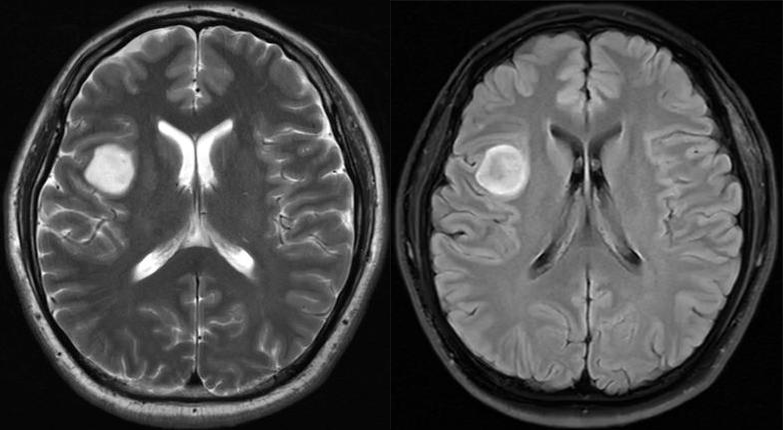

2 例星形细胞瘤 IDH 突变型,均表现为 T2-FLAIR 错配,注意 FLAIR 低信号可以是均匀或不均匀

1 例星形细胞瘤 IDH 突变型,均表现为 T2-FLAIR 错配